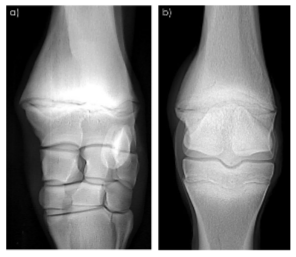

• Clinical signs of physitis include heat, swelling, pain on palpation and possibly lameness. This condition is commonly bilateral and occurs in the forelimbs. Radiographs will show widening, sclerosis and periosteal new bone with bridging

• what condition can be seen on this image?

physitis